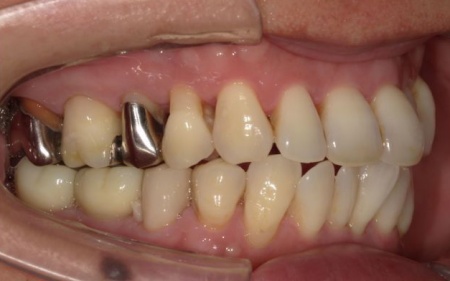

また、右下奥歯には、両隣の歯を土台にして橋を渡すように欠損部を補う被せ物「ブリッジ」が装着されていました。

右下奥歯は2本欠損しており、親知らず(第3大臼歯)と手前の奥歯(第2小臼歯)の2本でブリッジを支えていますが、これは親知らずに過度な負荷がかかる構造です。

親知らずはすでに大きく傾いており、こちらも温存が難しいため、ブリッジを除去してから親知らずを抜く必要があります。

次に、右下に装着されているブリッジを除去してから右下の親知らずを抜き、欠損部(第1大臼歯、第2大臼歯の部分)にインプラントを埋入しました。

また、右下の手前にある奥歯2本(第1小臼歯、第2小臼歯)は、新しく詰め物を作製して噛み合わせと見た目を整えています。